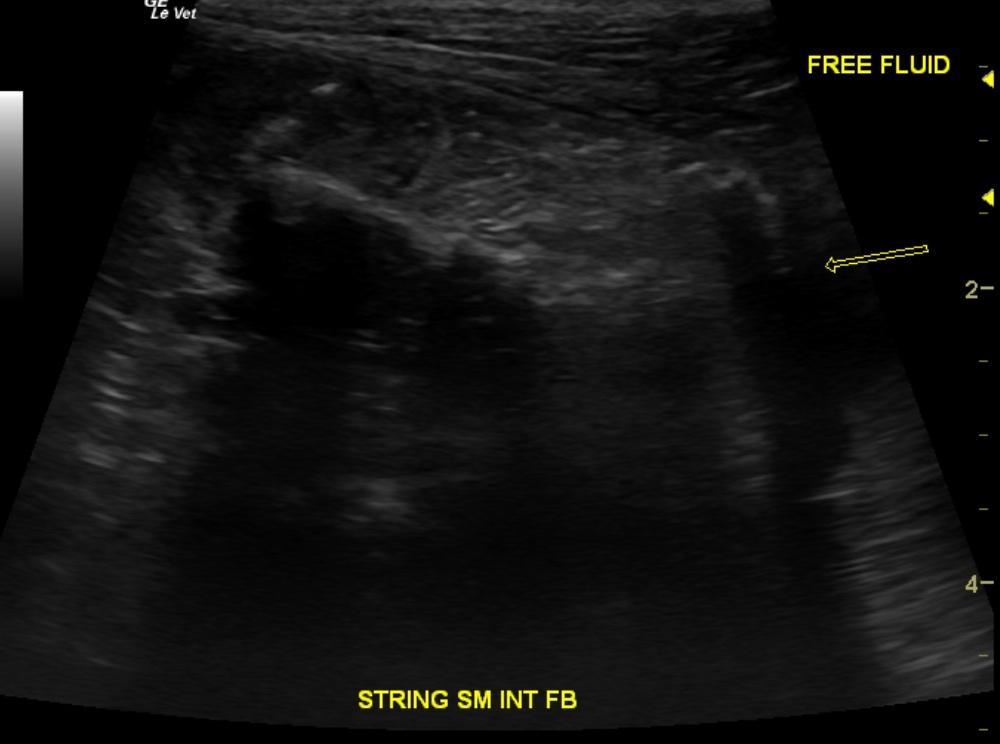

Video 1: Gastric dilation with a 5cm highly irregular shadowing foreign material that entered the duodenum and continued into distal small intestines. Video 2: Aggressive accordion shape and an ill defined intestine and mesentery. A minor amount of free fluid (arrow).